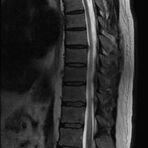

- Abklärung Bandscheibenvorfall

- Beurteilung Einengung des Rückenmarkkanals oder der Neuroforamina im Rahmen der degenerativen Wirbelsäulenerkrankung

- Tumor-/Entzündungsdiagnostik

- Multiple Sklerose

- Abklärung Spondylolisthesis

- Frakturdiagnostik (Alter und Ausdehnung der Fraktur) z.B. im Rahmen der Osteoporose